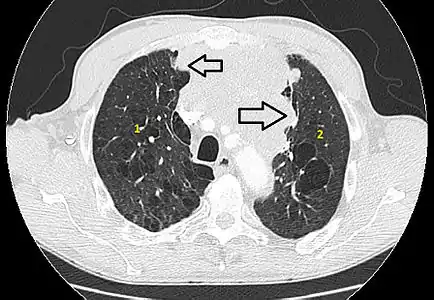

Scanner en fenêtre parenchymateuse, montrant un carcinome thymique envahissant les poumons (avec des lésions d'emphysème) au contact des deux poumons (1 : poumon droit ; 2 : poumon gauche) ;

flèches noires : zones suspectes d'envahissement.